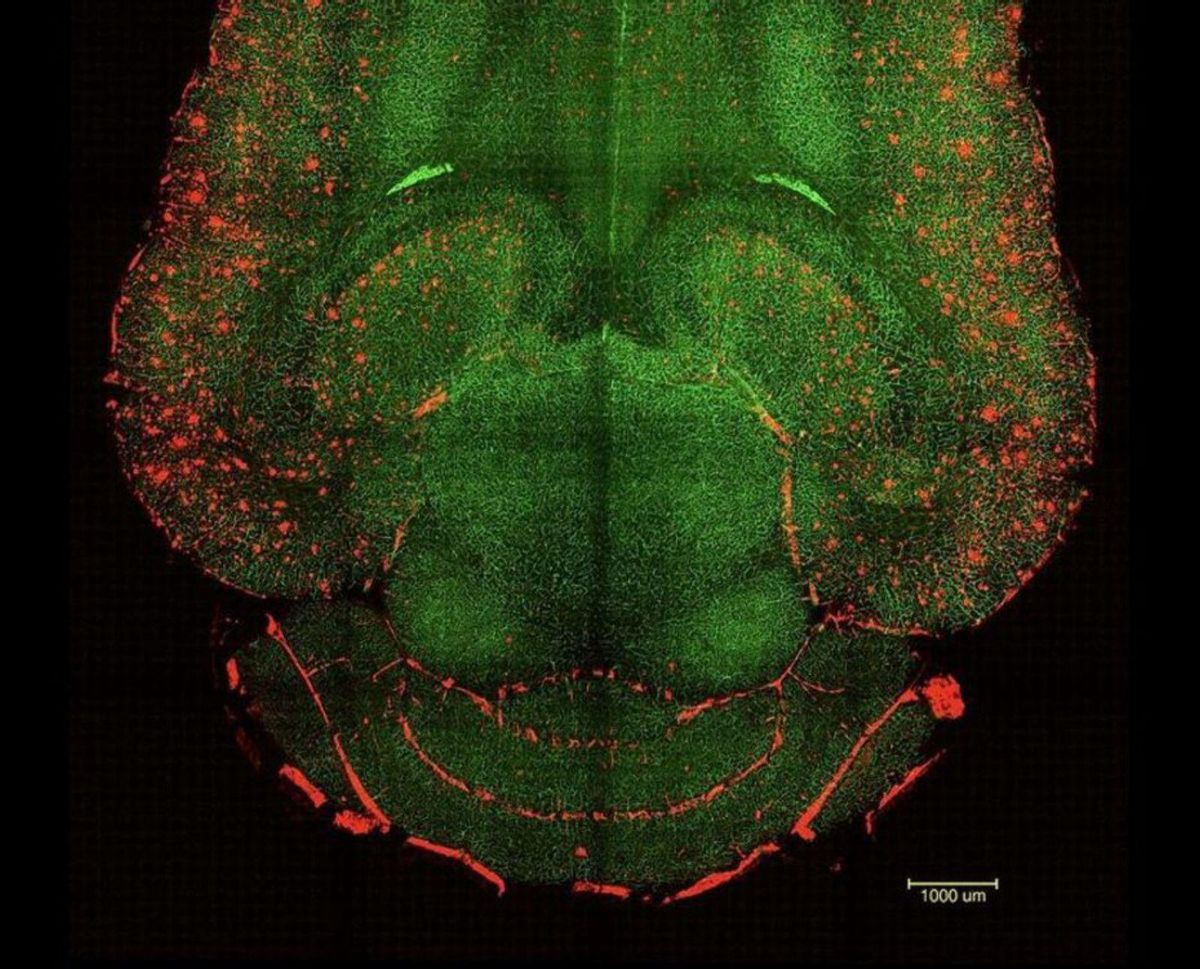

L’estudi, publicat ahir, destaca pel seu enfocament. En lloc de centrar-se a abordar les neurones afectades per la malaltia o en les proteïnes que la provoquen, els investigadors han apostat per dissenyar un tractament per "restaurar la funció de la barrera hematoencefàlica", una estructura essencial que regula el pas de substàncies entre la sang i el cervell. És a dir, s’han centrat a restaurar el "gran guardià" que protegeix el cervell de toxines, patògens i altres amenaces, com per exemple l’acumulació de proteïnes que bloqueja els sistemes naturals d’eliminació de rebuigs i desencadena el deteriorament neuronal de l’Alzheimer.

Per a això, un equip dirigit pel professor Giuseppe Battaglia, investigador ICREA a l’IBEC, es va centrar en el disseny de nanopartícules bioactives capaces de restaurar la funció normal d’aquesta barrera al cervell de ratolins amb Alzheimer. Segons els responsables del treball, aquestes partícules actuen com a "fàrmacs supramoleculars" que, a diferència d’altres compostos que actuen com a simples transportadors de medicaments, en aquest cas funcionen com a "agents actius" que no només interactuen amb els receptors cel·lulars, sinó que, a més, treballen per reactivar el mecanisme de neteja cerebral.

Notícies relacionades"Només una hora després de la injecció vam observar una reducció del 50% al 60% de la quantitat de les proteïnes amiloides al cervell, principals causants d’aquesta malaltia", explica Junyang Chen, primer coautor de l’estudi i membre de l’Hospital West China i de la University College London.

Aquesta teràpia es va aplicar en ratolins de 12 mesos, l’equivalent a 60 anys en humans, amb símptomes d’Alzheimer. En hores es van començar a veure canvis al seu cervell i dies més tard ja es van veure canvis positius en el seu comportament i memòria. Sis mesos després, quan els animals tenien el cervell d’un nonagenari, ja no mostraven símptomes de la malaltia, sinó que es comportaven com a exemplars completament sans.